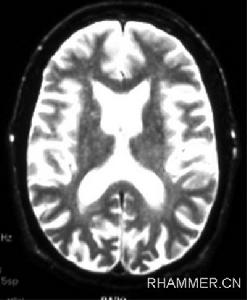

該病以運動障礙、痴呆和精神行為異常為主要臨床表現。90%的亨廷頓病患者中,舞蹈樣動作是最常見的運動障礙。舞蹈動作常自肢體遠端開始,病情進展時逐漸發展為全身性並影響隨意運動。其病理改變包括神經元缺失和神經膠質增生,主要見於大腦皮質和紋狀體。